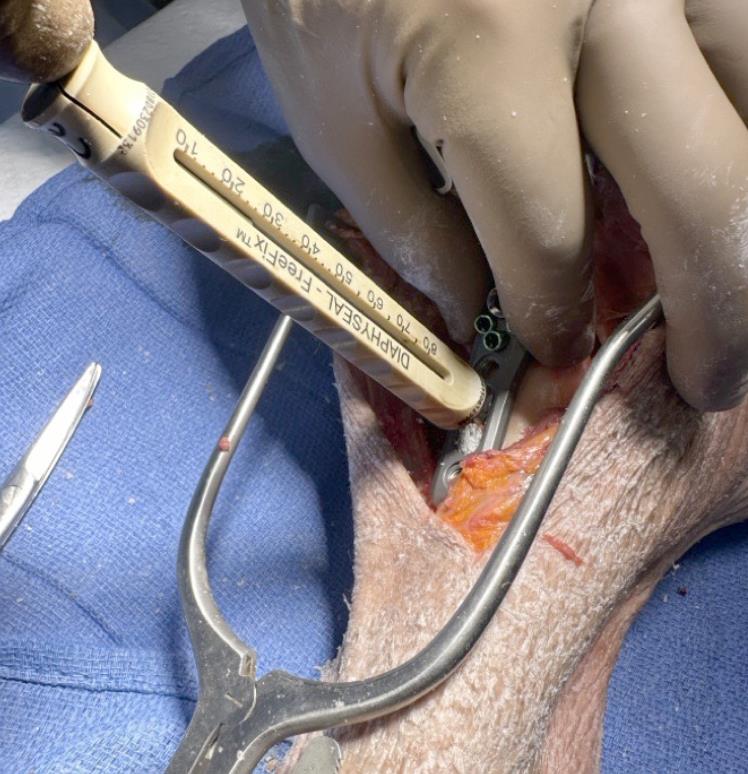

• Metaphyseal peg and screw preparation

• Polyaxial drill guides (PDGs) are inserted into the metaphyseal holes to direct drilling.

• For 3.5 mm smooth locking pegs, a 3.5 mm drill is used to perforate the near cortex.

• For 3.7 mm metaphyseal screws or 3.5 mm variable-angle screws, a 3.0 mm drill is used.

• The technique guide cautions against advancing drills beyond the cutting flutes to avoid articular penetration.

• The central K-wire can be bent if necessary to avoid interference with drilling in other holes.

• Manual safe-tip drilling and subchondral preparation

• After near-cortex drilling, subchondral preparation is performed with blunt safe-tip drills advanced manually through the PDGs.

• For pegs, a 3.5 mm blunt-tip drill is used; for screws, a 3.0 mm blunt-tip drill is used.

• These drills are advanced under fluoroscopic control to just shy of the subchondral bone, with the design intent that the implant tips rest several millimeters below the joint surface.

• Multiple manual passes can be used to clear bone debris and fine-tune depth.

• Peg or screw length is determined from the drill scale or with an AIMing guide or depth gauge, depending on surgeon preference and instrumentation.

• Peg and screw insertion

• After drilling and measurement, PDGs are removed and the chosen 3.5 mm pegs or 3.7 mm screws are inserted.